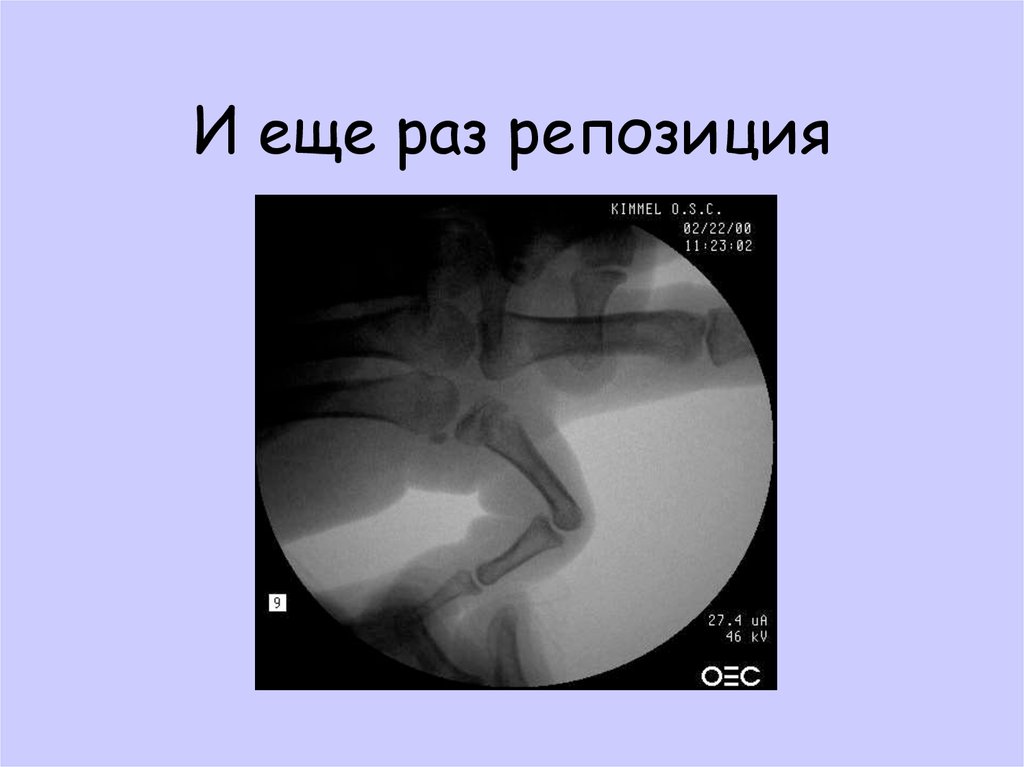

40. И еще раз репозиция

41. И еще раз репозиция